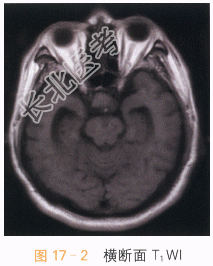

读片分析:头颅CT平扫见鞍上异常软组织影,并可见多发钙化,局部见“蛋壳样钙化”,横断面T₁W见鞍上异常软组织信号灶,呈等高信号影,T₂WI见病灶表现为囊实性肿块;增强扫描实性部分可见明显强化,囊性部分未见明显强化,但正常垂体结构能显示。结合患者临床,可考虑颅咽管瘤。